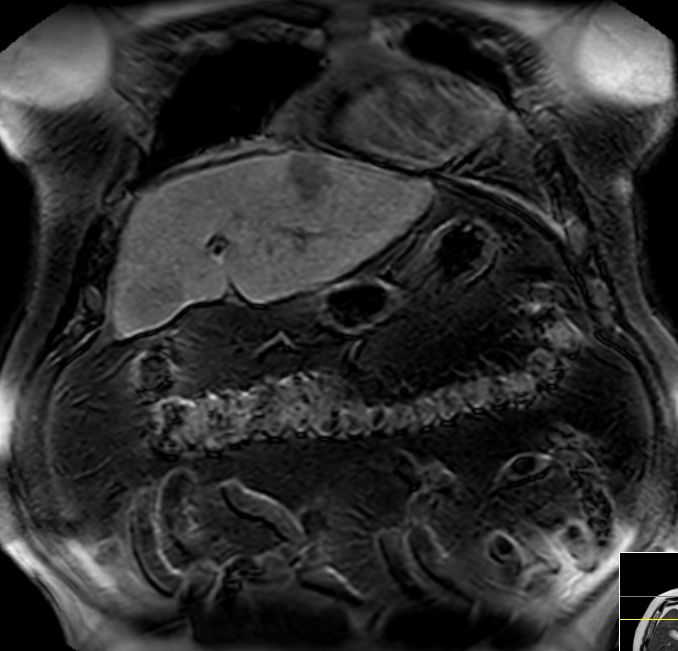

| intrahepatische Filiae | 68-jähriger Mann mit bekannter Leberzirrhose nach Alkoholabusus.

Im CT mehrere hypervaskuläre Herde gesehen.

Im MR beste Darstellung auf den Spätaufnahmen nach leberspezifischem Kontrastmittel in der hepatobiliären Ausscheidung.

Unterhalb der Zwerchfellkuppel links subkapsulär ventral gelegener Herd im 2. Segment 34 mm.

In der koronaren Schichtung im 8.Lebersegment ein 8,5 mm kleiner signalabgesenkter Leberherd.![]() |